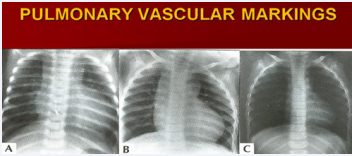

Figure 3 Chest roentgenograms (Postero-anterior views) of a baby with tricuspid atresia showing an enlarged cardiac size and increased pulmonary vascular markings (A); during follow-up, the size of the heart diminished and the pulmonary vascular markings decreased (B & C). Echocardiographic and angiographic studies demonstrated a progressive decrease in the size of the ventricular septal defect [17].

Figure 3: Chest roentgenograms (Postero-anterior views) of a baby with tricuspid atresia showing an enlarged cardiac size and increased pulmonary vascular markings (A); during follow-up, the size of the heart diminished and the pulmonary vascular markings decreased (B & C). Echocardiographic and angiographic studies demonstrated a progressive decrease in the size of the ventricular septal defect [17].

As mentioned above, spontaneous closure of VSD in Type I patients will result in progressive decrease in the size of the heart and of the pulmonary vascular markings as shown in Figure 3.

The greatest value of the chest X-ray is its capacity to classify babies into those that have diminished pulmonary vascular markings and into those with increased pulmonary vascular markings. Frequently, this is all that is needed to formulate an accurate diagnosis once a history, physical examination, and Electrocardiogram (ECG) have been acquired [33].